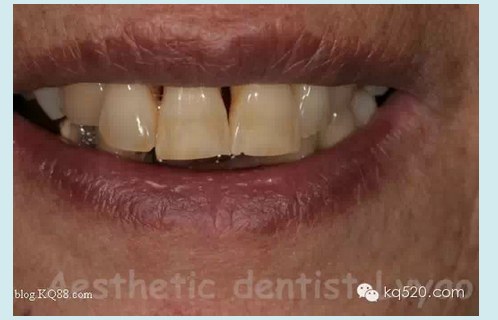

修復(fù)前口外影像